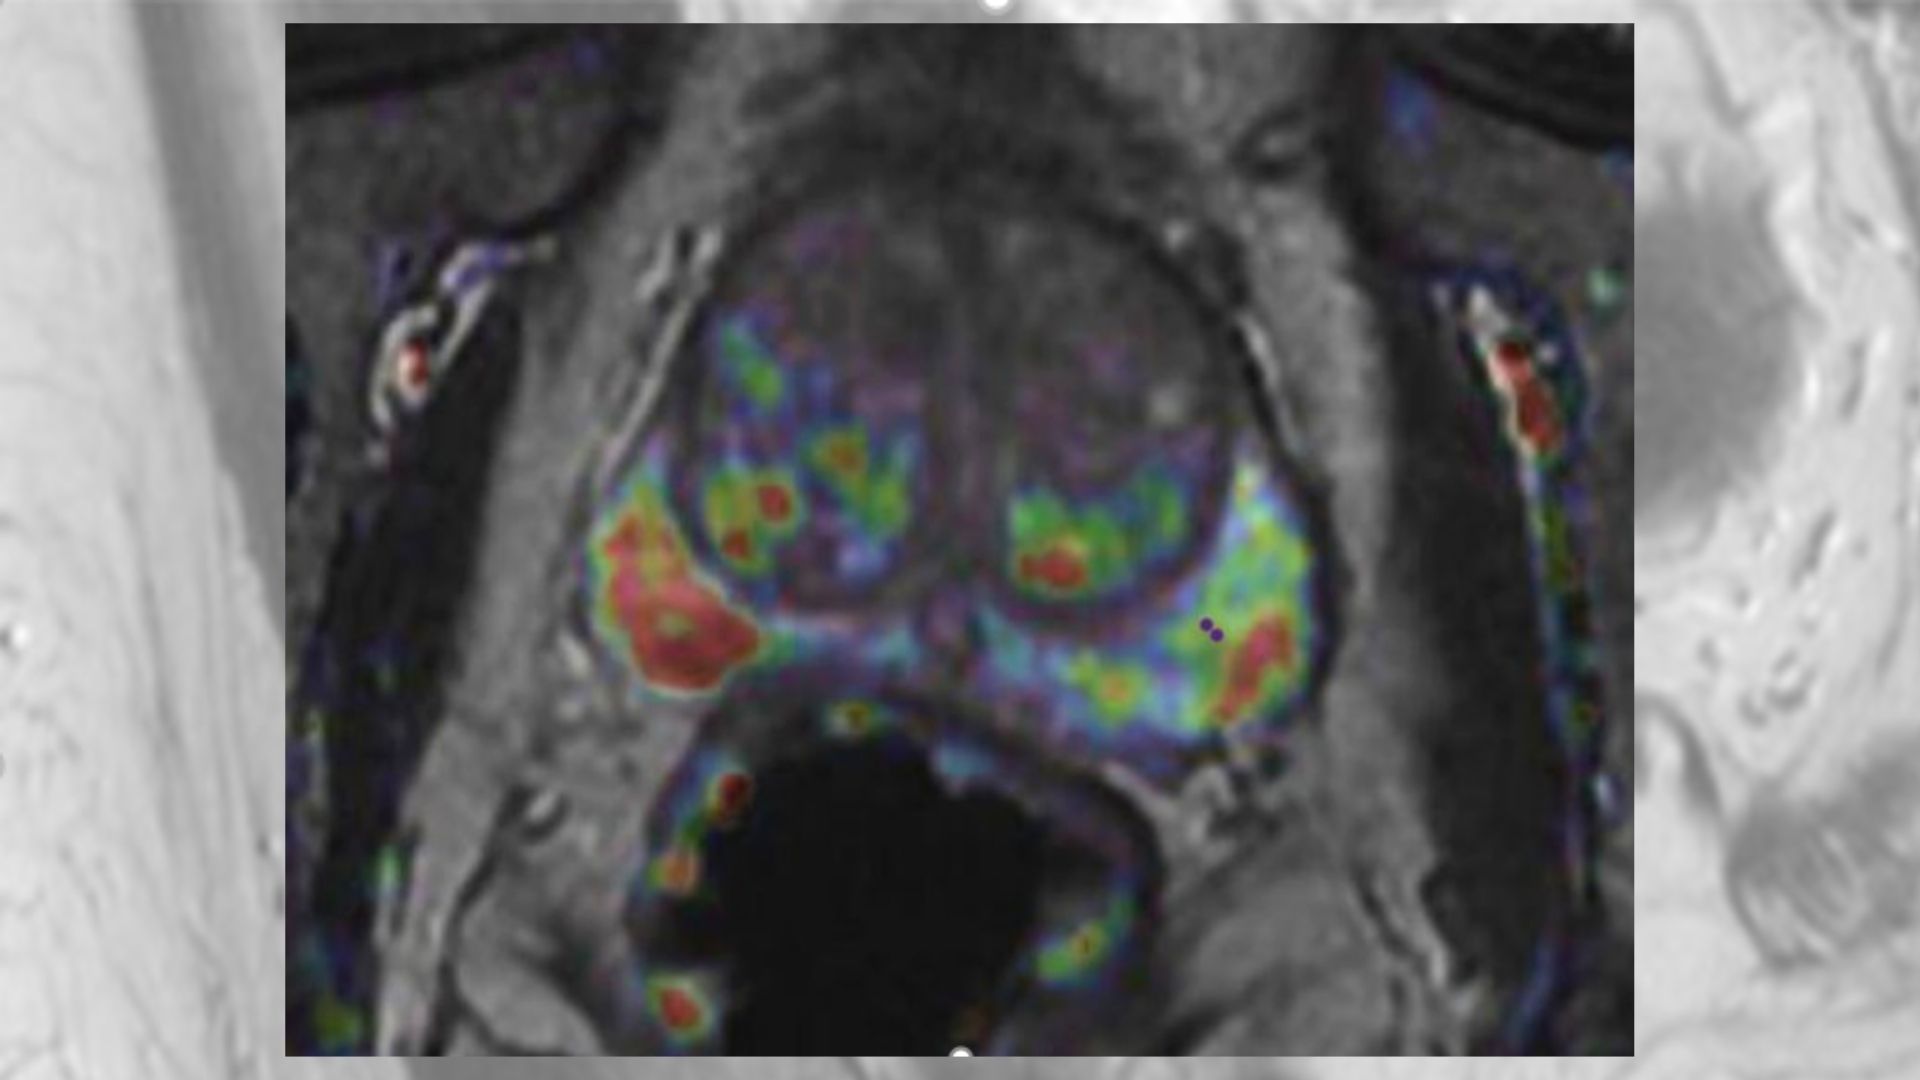

Comprender de manera práctica las variaciones en la puntuación de las .1的要点进行解读。Repasar las claves del Sistema PI-RADS v2.1 clarifies that T2-weighted images should be obtained in the axial plane (either straight to the patient or in an oblique axial plane matching the long axis of the prostate) and in at least one additional orthogonal plane. C/ Alcalá, 135 1º | 28009 – Madrid + 34 91 575 26 . El informe generalmente incluye seis secciones: Tipo de examen. Conoce el resto de las ponencias: 1. Prostate MRI: practical guidelines for interpreting and reporting according to PI-RADS version 2. 日本は他の先進国と比較して人口当たりのMRI装置は多く、人間ドックなどにおいても前立腺のMRI検査は数多く施行されていますが、その 読影方法の標準化がされてこなかった という背景があります。 “1 is the new 6” – a simplified version of the Gleason grade system designed by urologists to help patients understand risk level GG1 . Si tratta di uno score (o scala) PI-RADS (pirads V2) che indica il rischio della presenza di un carcinoma. Resonancia magnética de próstata: guía práctica de interpretación e .PI-RADS version 2.Objetivos: Conocer las principales novedades del sistema de estadificación PIRADS en su versión 2.1 is designed to improve detection, localization, characterization, andrisk stratification in patients with suspected cancer in treatment naïve prostate glands. ¿Cómo se utiliza en los centros médicos?, 3+4=7) based on the 2 highest proportions of the most aggressive pattern in each biopsy needle sample. Sánchez-Oro, R . Torres Nuez, G.2019年前列腺成像报告和数据系统(pi-rads)指导委员会发表了pi-rads v2. Historia clínica. Publicationdate 2018-08-01. Protección de personas y animales.PI-RADS (Prostate Imaging Reporting and Data System) – это система оценки данных и составления заключения при интерпретации МРТ предстательной железы с целью оценки вероятности присутствия клинически значимого рака. Descripción El carcinoma de próstata (CP) es la neoplasia no cutánea más prevalente . El objetivo de este . Jorge Eduardo Citelli Ramírez: Interpretación del electrocardiograma en el Holter.The Prostate Imaging Reporting and Data System (PI-RADS v2. 前立腺癌のMRI画像診断の問題点とPI-RADS version2が目指すもの.

Please cite this article as: Sánchez-Oro R, Torres Nuez J, Martínez-Sanz G, Grau Ortega Q, Bleila M. El sistema de datos e informe en imagen prostática (Prostate Imaging and Reporting and Data System, PI-RADS) en su versión 2 fue creado con el fin de ayudar en la detección, localización y caracterización del cáncer de próstata con resonancia magnética (RM).Prostate MRI: practical guidelines for interpreting and reporting according to PI-RADS version 2. In questo articolo si analizza cos’è il pirads, cosa indica, cosa significa e quali implicazioni ha in pratica.El documento PI-RADS v2 es sencillo de aplicar a la lectura de la RMmp de próstata.This document presents PI-RADS v2, which provides guidelines for the acquisition, interpretation, and reporting of multiparametric MRI (mpMRI) of the prostate.

Opciones para .Recientemente, en marzo de 2019, se publicaron los nuevos criterios PIRADS versión 2.1 / Prostate MRI: practical guidelines for interpreting and reporting according to PI-RADS version 2.Respecto a su informe. Los autores declaran que para esta investigación no se han realizado experimentos en seres humanos ni en animales. Esta guía estandariza la técnica de adquisición de imágenes con recomendaciones sobre los requerimientos mínimos de secuencias e interpretación de los hallazgos.Consulte los artículos y contenidos publicados en este medio, además de los e-sumarios de las revistas científicas en el mismo momento de publicación.1 for estimating the probability and zonal location of significant tumors of the prostate, using a practical approach that includes current considerations about the prerequisites for carrying out the test and recommendations for interpreting the findings.

Esté informado en todo momento gracias a las alertas y novedades. Acceda a promociones exclusivas en suscripciones, lanzamientos y cursos acreditados .Il Pirads è un punteggio (da 1 a 5) che indica quanto un reperto riscontrato in risonanza è sospetto per essere un tumore prostatico.Revisamos los conceptos del sistema PI-RADS versión 2. Promociones exclusivas. Máxima actualización.This article reviews the concepts in PI-RADS version 2.Prostate Cancer – PI-RADS v2. 3D T1W GRE is preferred.1 for estimating the probability and zonal location of significant tumors of the prostate, using a practical approach that .

笔者对vi-rads v2.PI-RADS v2 is designed to standardize image acquisition techniques and interpretation of prostate MRI, which is critical for management, communication, comparative research .1 updates the technical parameters for multiparametric MRI (mpMRI) of the prostate and revises the imaging interpretation criteria while maintaining the .Resonancia magnética de próstata: guía práctica de interpretación e informe según PI-RADS ; Resonancia magnética de próstata: guía práctica de interpretación e informe según PI-RADS versión 2. Usefulness of Prostate-Specific Antigen Density as an Indicator for . En 2007, reconociendo la importancia creciente de la RM en la evaluación del cáncer de próstata, la Fundación AdMeTech reunió en un grupo de trabajo internacional a los líderes de la investigación académica e industrial sobre este tema. Grau Ortega, M. PI-RADS categories communicate the . Esta sección enumera: Martínez-Sanz, Q., Martínez-Sanz, G.Profundizar en el postproceso e informe PI-RADS con una nueva herramienta, ProView, estructurada y pautada en base a PI-RADS v2. Una buena oportunidad para ampliar los conocimientos sobre el informe PI-RADS de la mano de GE Healthcare.1) es la versión actual. Breve revisión actualizada del PI-RADS en RMmp para el diagnóstico y manejo del paciente con sospecha de cáncer de próstata. Tercer curso anual de Cardiología: manejo avanzado de las patologías cardiovasculares.El correcto manejo de la RM requiere conocer y utilizar de forma eficaz las distintas guías elaboradas para la adquisición, interpretación e informe de la RM en el diagnóstico (guía PI-RADS), estadificación de cuerpo entero (guía MET-RADS), vigilancia activa (guía PRECISE) y recidiva local (guía PI-RR) en el cáncer de próstata.Este webinar tiene como objetivos: 1.